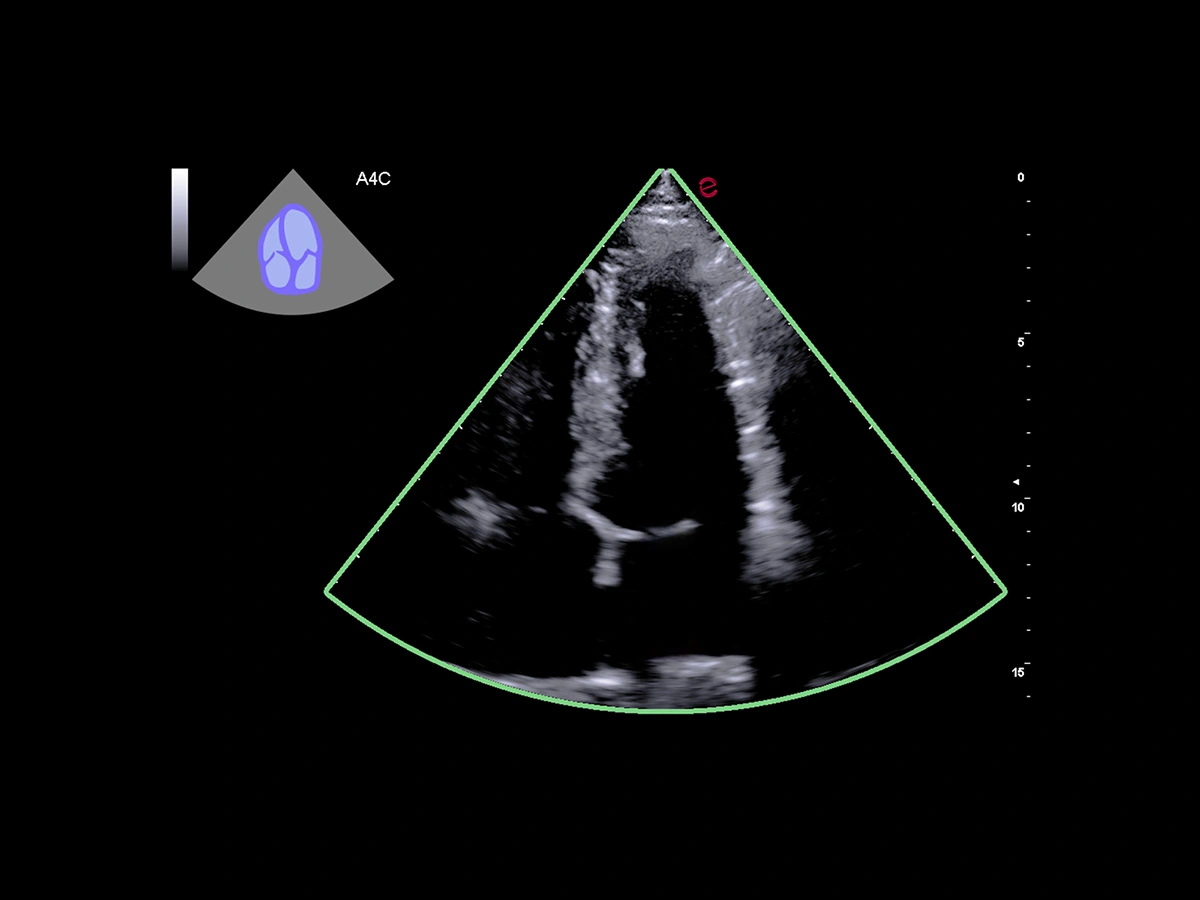

Outstanding image quality

Esaote’s XCrystal probe PX1-5 delivers exceptional clarity in B-Mode imaging, providing deep penetration and excellent resolution even in technically challenging patients. Its advanced architecture ensures high Doppler sensitivity and spatial detail, enabling an accurate assessment of wall motion, valve morphology, and flow dynamics. From subtle endocardial borders to low-velocity diastolic flows, the PX1-5 probe ensures you never miss the details that matter.

Esaote’s HeartScan Assistant supports clinicians during echocardiographic exams by automatically recognizing the scanning plane and displaying it on the screen. The ultrasound sector is highlighted with a color-coded overlay that indicates the confidence level of the recognition, providing immediate visual feedback. This intelligent, AI-based feature is therefore designed to support operators in image acquisition during routine practice.

Clinical images